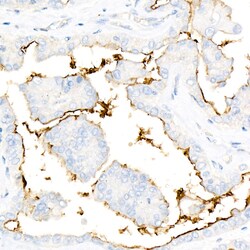

ICAM-1 Recombinant Monoclonal Antibody for Western Blot, ICC/IF, IHC (P), ELISA

| ELISA, Immunohistochemistry (Paraffin), Western Blot, Immunocytochemistry | |